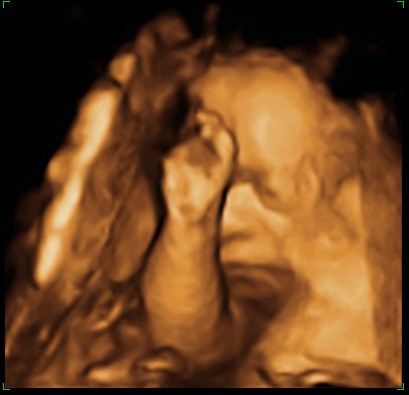

... Wrzucam zdjęcia z ubiegłej środy, czyli 28 tydzień z hakiem.